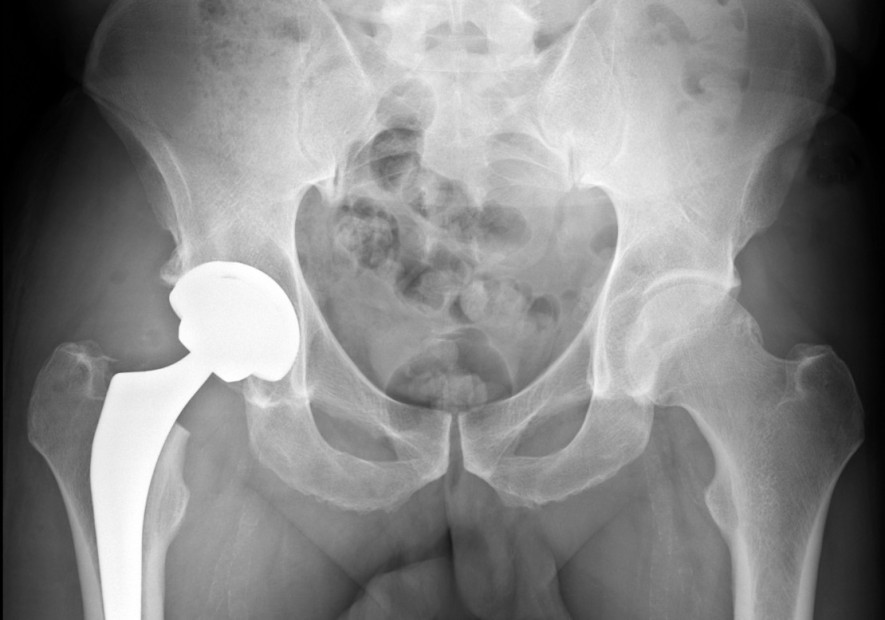

¿Cómo se diagnostica la artritis?

El dolor es a menudo el primer síntoma que conduce a la consulta. Una radiografía generalmente confirma el diagnóstico, revelando anomalías en la estructura articular. Además, pruebas como la resonancia magnética pueden ser útiles para evaluar la condición de tejido blando y cartílago con mayor precisión.